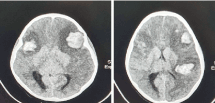

On initial examination, her Glasgow coma scale (GCS) was 15, with pupils equal and reactive bilaterally. A complete blood count revealed a platelet count of 26 x 109 /L and a computed tomography of the brain without contrast was performed. It showed the presence of the three distinct foci of hyper-densities in keeping with, cerebral contusions. A left frontal lobe contusion of 2.6 cm x 2.3 cm, a right frontal lobe contusion of 1.8 cm x 1.5 cm and left parietal lobe contusion 1.8 cm x 2.3 cm. There was no evidence of midline shift and the dimensions of the ventricular system remained within normal limits (Figures 1 and 2).

Figure 1. Computed tomography of the brain (axial view) showing A. cerebral haemorrhage in bifrontal regions and B. cerebral haemorrhage in left parietal region

Figure 2. Computed tomography of the brain (coronal view) showing A. cerebral haemorrhage in bifrontal regions and B. cerebral haemorrhage in left parietal region